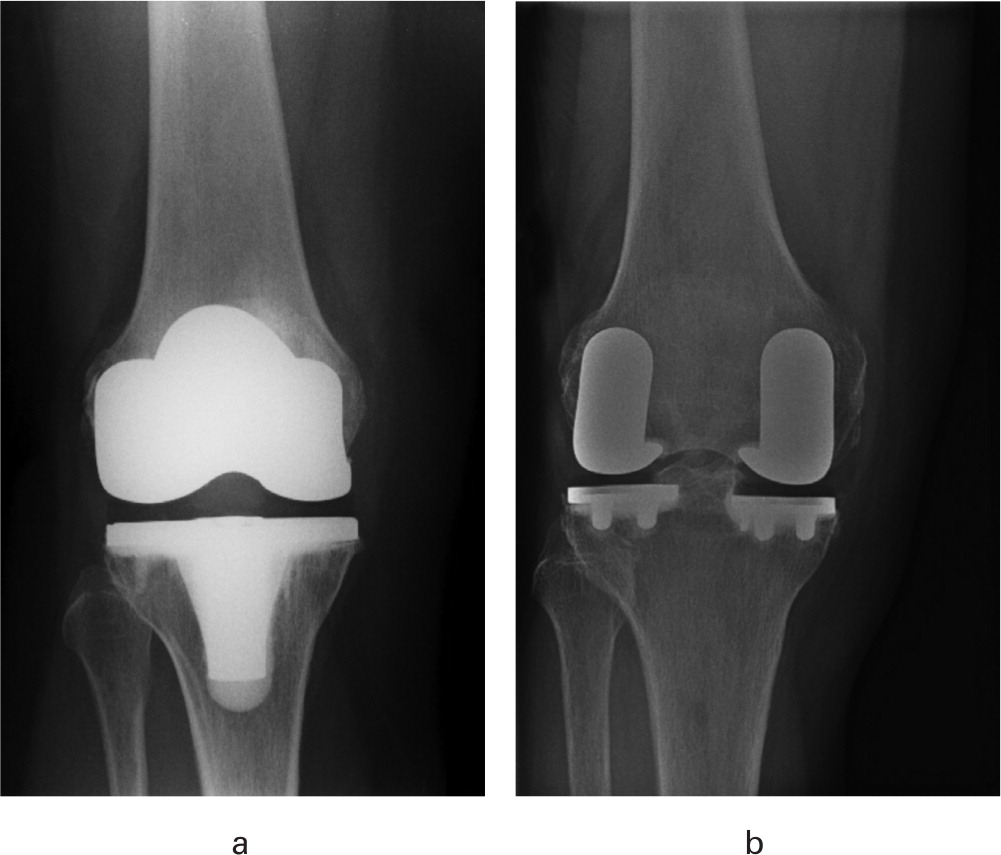

TRUCK RCT: Biomechanical function outcomes published in the Bone & Joint Journal online.boneandjoint.org.uk/doi/full/10.13… James Doonan Ortho-GRI Biomed Engineering